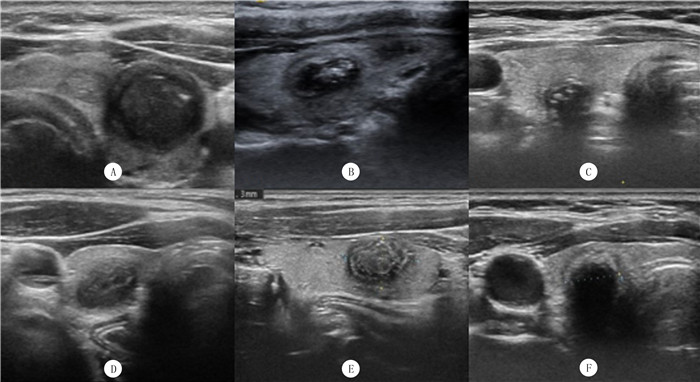

在高频声像图上,“双边征”多表现为平行/近乎平行的两个环,可占据结节一半以上的边缘部(图 2A~C):内环纤细连续,为等/略高/强回声;外环略厚或厚薄欠均匀,为低回声。内环的病理基础为皱缩过程中未被累及或遮挡而保留下来的囊壁结构,外环则为皱缩的囊壁、炎性反应带、纤维化等。值得注意的是,“双边征”在结节不同固缩状态下,有不同的表现,如囊壁收缩征[49]、指纹征或同心圆征[49]和壳状钙化等。囊壁收缩征:是指结节边缘的高回声晕,通常不完整,在其外缘可见裂隙样低回声。指纹征:当某一个方向上(如水平位)吸收比较少,而垂直位吸收比较多时,声像图表现为低回声环和高回声环呈条纹状交错出现(图 2D)。同心圆征:各方位对称性吸收,声像图表现为一个完整的低回声晕和高回声环相互嵌套而成,中央为尚未完全吸收的液性成分(图 2E)。当囊液完全被吸收后,结节进入木乃伊化的终末阶段,边缘的高回声环形成壳状或弧形强回声(图 2F)。另外,“双边征”中的低回声外环需要与PTC周边的低回声晕相鉴别,PTC的低回声晕与癌结节纤维假包膜、周边绕行血管、周围组织受压或浸润等有关[7, 46]。TAN等[49]研究表明,19.7%的MNs和37.6%的PTC可以发现晕征。因此,晕征不能鉴别良恶性结节。

![]() |

| A~F为MNs“双边征”,A、B、C显示双边分别占据结节周长的100%、75%、50%;D、E、F分别为MNs“指纹征”、“同心圆征”、壳状钙化。 图 2 MNs“双边征”的高频超声声像图特征 |